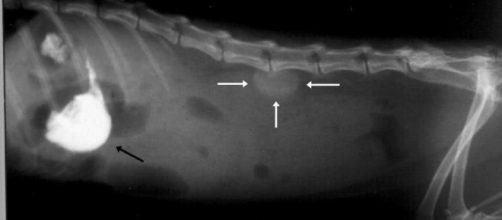

En los caninos, es frecuente la presencia de juguetes, huesos, pelotas, piedras y anzuelos, mientras que en los gatos suele ser más frecuente la ingestión de cuerpos extraños lineales como un hilo o cuerdas,

La intususpección intestinal es una invaginación de un segmento intestinal dentro del segmento intestinal adyacente; éstas aunque se pueden observar en cualquier segmento del intestino, frecuentemente son detectadas a nivel del orificio ileocecocólico; esta patología es mucho más frecuente en el perro que en gatos.